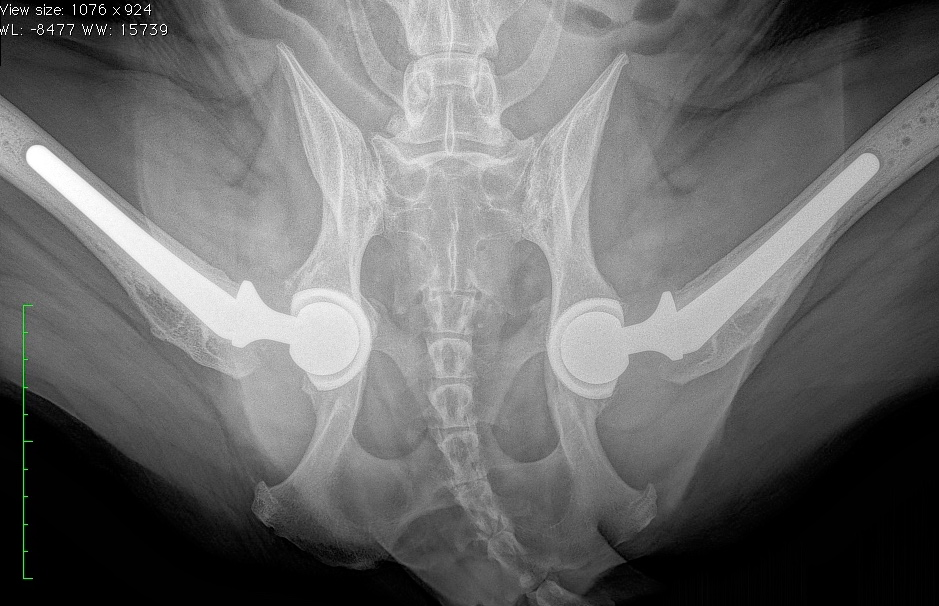

Total Hip Replacement Canine . The goal of a total hip replacement is to restore normal function to the hip joint, and alleviate the pain and discomfort associated with hip dysplasia. A total hip replacement (thr) is a surgical procedure during which the entire hip joint is replaced. Total hip replacement surgery removes and replaces both the ball and socket with prostheses (artificial parts). Total hip replacement (thr) is used for dogs and cats of all ages. The thr procedure is commonly performed to treat pain and disability associated with hip dysplasia and degenerative osteoarthritis conditions. Prosthetic implants used in a thr fit with precision and mimic the original joint anatomy and function. This creates a new joint for the body. Most canine hip replacement prostheses have a metal ball at the top of the. The most frequent indication for total hip replacement in dogs is the relief of pain and lameness caused by severe arthritis secondary. Total hip replacement in dogs is a procedure where the entire arthritic hip joint is replaced with a prosthesis, including the stem (within the femur), ball (femoral head) and socket (acetabulum). There are different types of implants that can be used for your pet and vary in composition.

Total hip replacement surgery removes and replaces both the ball and socket with prostheses (artificial parts). There are different types of implants that can be used for your pet and vary in composition. Total hip replacement (thr) is used for dogs and cats of all ages. The most frequent indication for total hip replacement in dogs is the relief of pain and lameness caused by severe arthritis secondary. This creates a new joint for the body. A total hip replacement (thr) is a surgical procedure during which the entire hip joint is replaced. Most canine hip replacement prostheses have a metal ball at the top of the. The thr procedure is commonly performed to treat pain and disability associated with hip dysplasia and degenerative osteoarthritis conditions. Prosthetic implants used in a thr fit with precision and mimic the original joint anatomy and function. Total hip replacement in dogs is a procedure where the entire arthritic hip joint is replaced with a prosthesis, including the stem (within the femur), ball (femoral head) and socket (acetabulum).